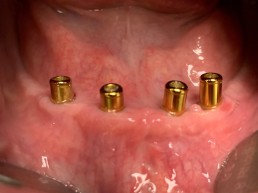

1. Locatoren/Druckknöpfe:

Prinzipiell die einfachste Art der Befestigung. Einfach zu reinigen. Bietet einen guten Halt, aber nicht den perfekten Halt. Leichte Kippungen und Wackeln sind möglich, man verliert die Prothese aber niemals. Es ist hier notwendig, dass nach der Fertigstellung, in manchen Fällen einmal pro Jahr, immer wieder Teile am Zahnersatz getauscht werden müssen, da diese sich abnützen oder lockern. Kostet dann bei den Reparaturen nicht die Welt, ist aber auch nicht zu vermeiden. Manchmal sind auch Unterfütterungen notwendig.

2 Locatoren/Druckknöpfe im Unterkiefer als Minimallösung sind deutlich besser als keine Implantate zu haben und geben einen guten Halt. Bei nur 2 Implantaten entsteht aber rein physikalisch aber immer eine Rotationsachse, die eine Kippung erlaubt, vor allem beim Abbeißen vorne. Deshalb sind 3 oder 4 Implantate deutlich besser, weil die Rotationsachse damit verschwindet.

Jede Krankenkassa zahlt für 2 Locatoren im Unterkiefer und für 4 Locatoren im Oberkiefer einen Zuschuss, ebenso zur Prothese, sofern der zeitliche Anspruch gegeben ist. Nicht zuviel erwarten!